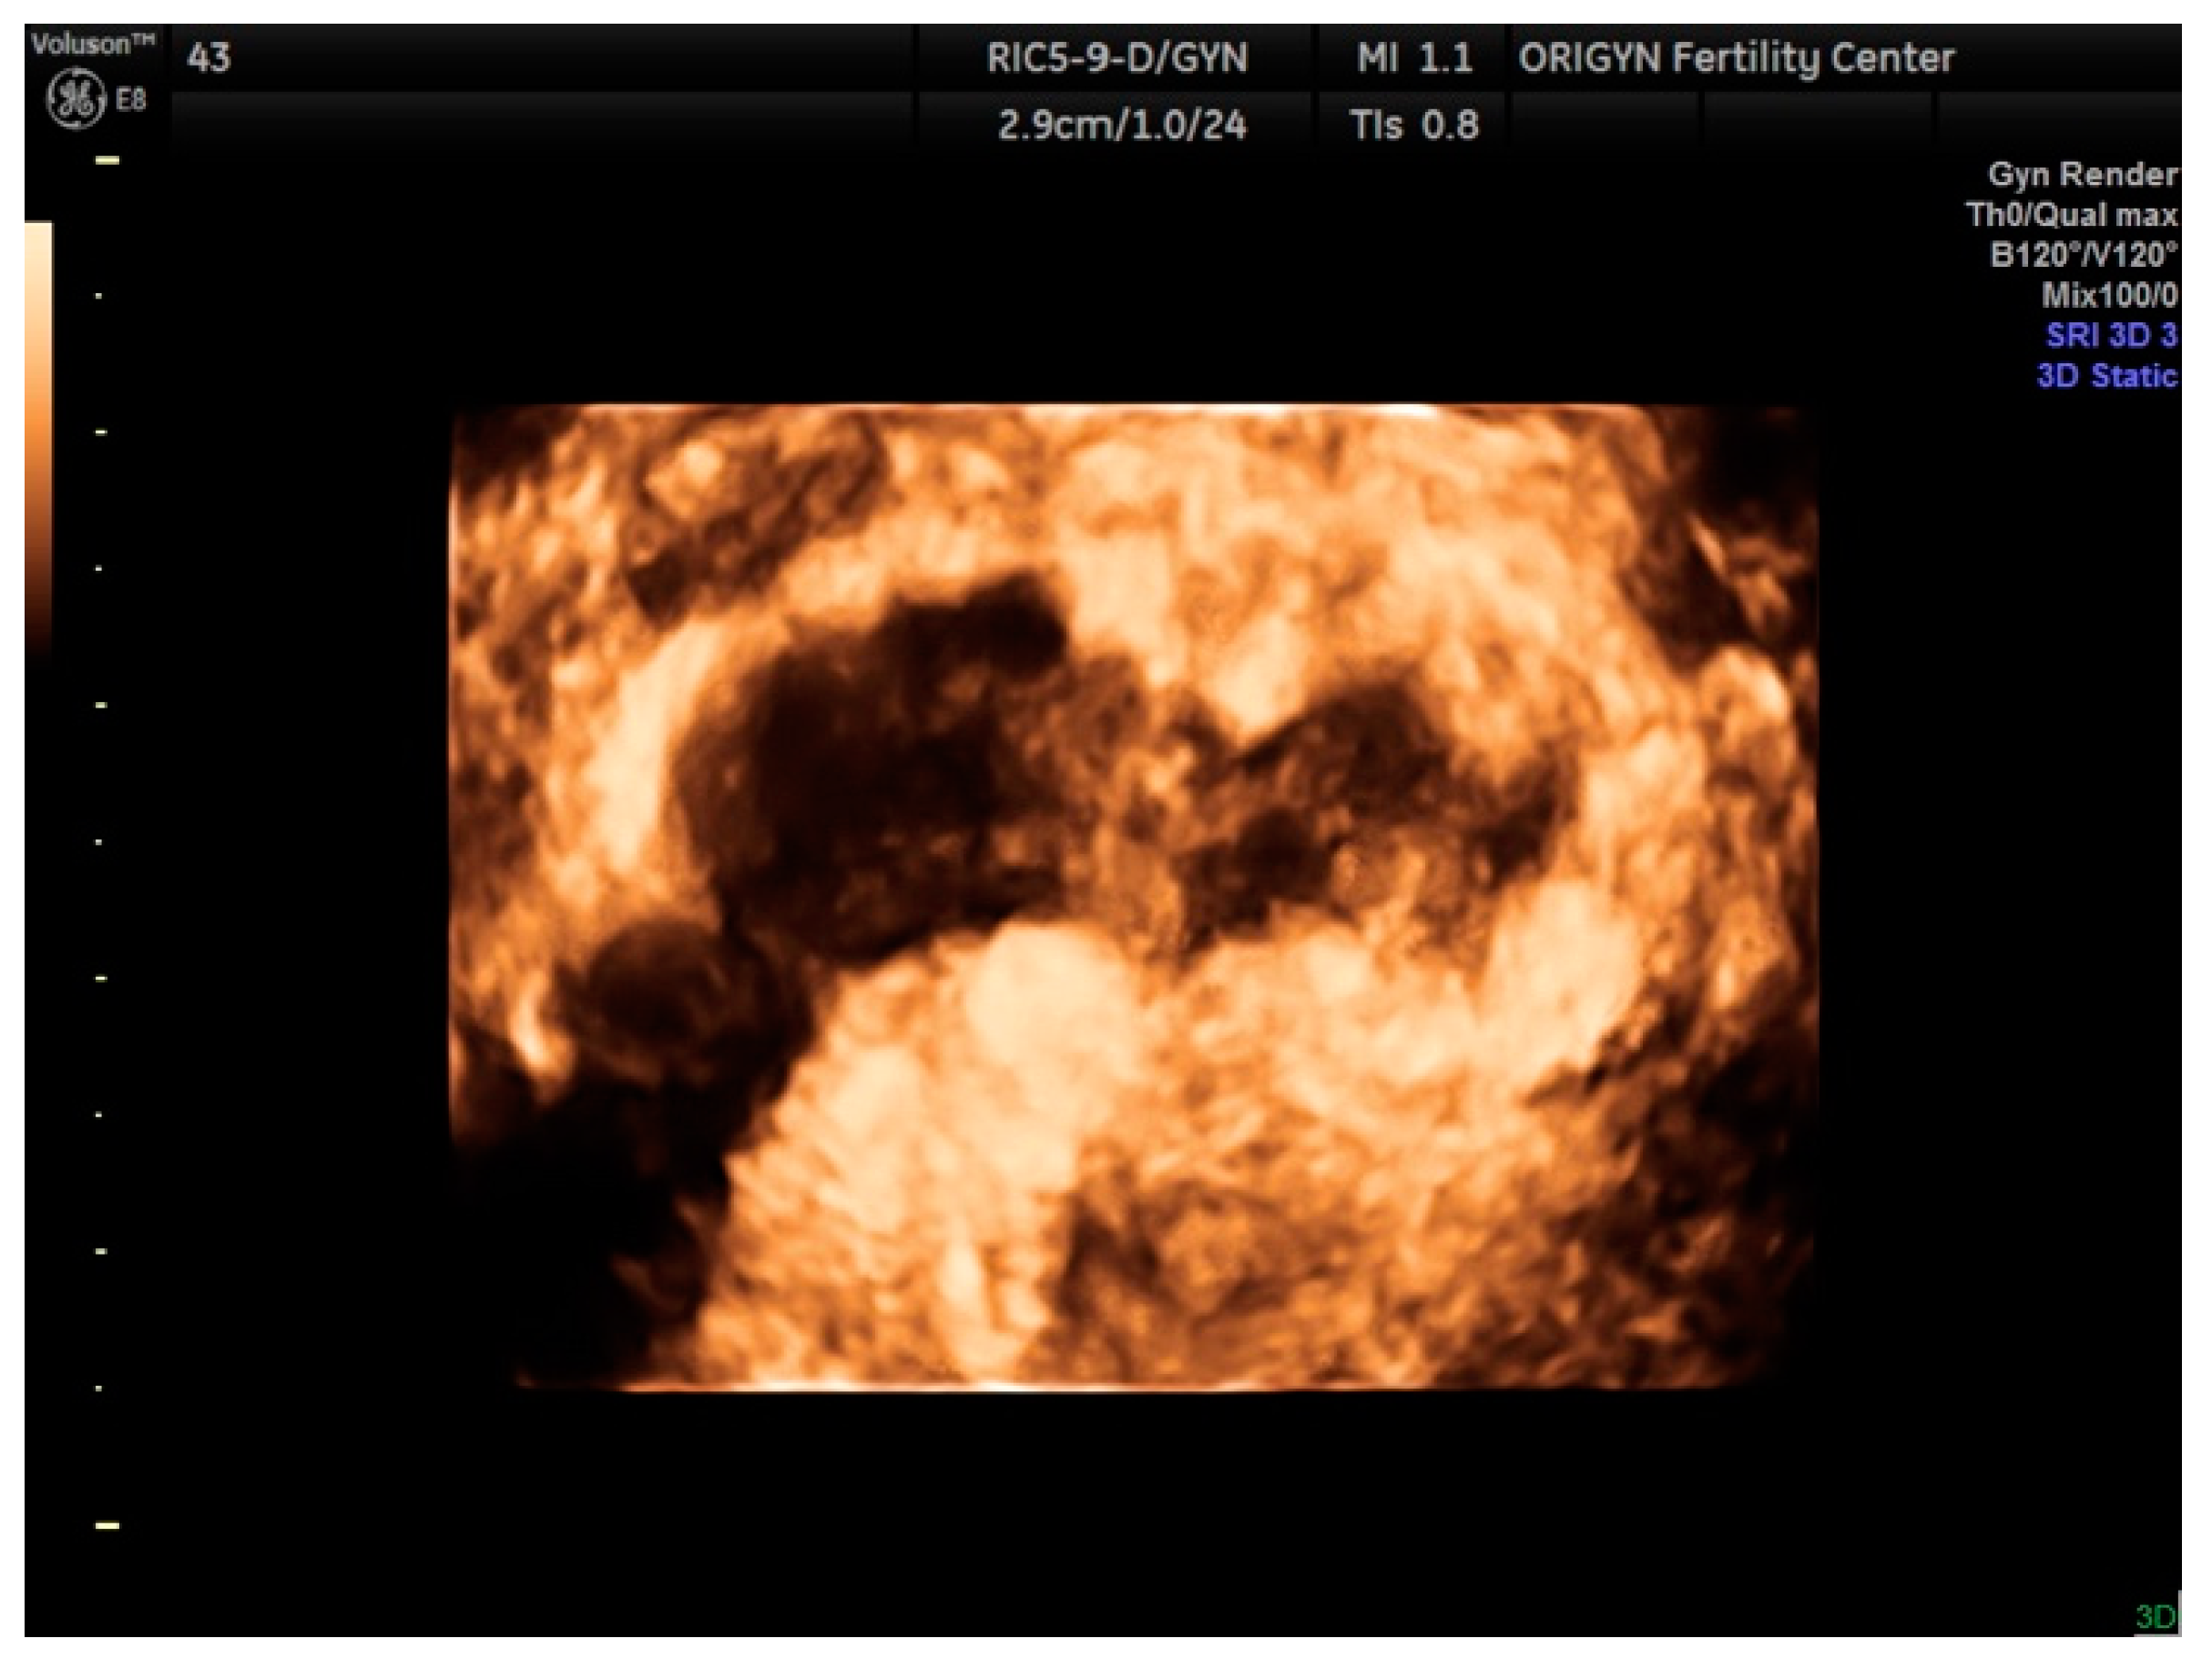

3.1. ADNEXA